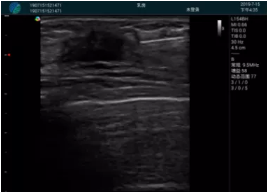

病例二:

腺體內部清晰顯示一低回聲塊影,形態(tài)不規(guī)則,邊界模糊,邊緣呈毛刺狀,內部見砂礫樣鈣化

M20引導下穿刺活檢術

M20引導下平面內穿刺取出的腫塊組織